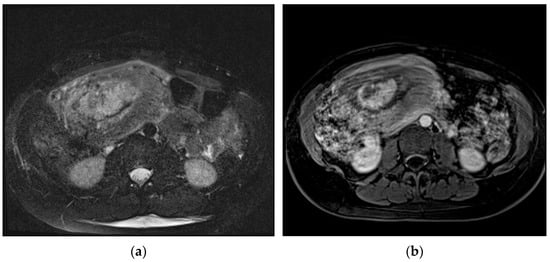

Placental/uterine bulge: deviation of the uterine serosa from the expected plane caused by abnormal bulge of placental tissue toward surrounding organs (typically toward the parametrium and bladder) can cause the uterus to take on an “hourglass” configuration due to widening of the lower uterine segment, resulting in a loss of the typical inverted pear-shape, best depicted on sagittal and/or coronal images. This finding showed a sensitivity and specificity for the diagnosis of PAS of 76.6% and 62.5% [72] (Figure 4). The specificity of this criterion increases where the bulging in the uterine contour is associated with a focal interruption of the myometrium [73].

MRI allows for the detection and characterization of large bladder flap hematomas (>4 cm in size) associated with UR or more often with UD (Figure 6).

When they are abscessed, large hematomas may cause fever and abdominal pain: in these patients, cross-sectional imaging reveals a peripheral-enhancing purulent collection between the lower uterine segment and the bladder wall (Figure 7).